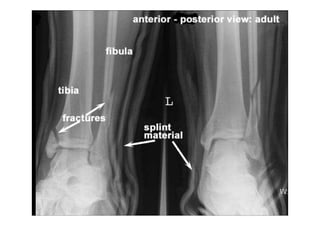

RADIOLOGIA DO

TRAUMA DO ESQUELETO

Referência: http://www.accessexcellence.org/RC/VL/